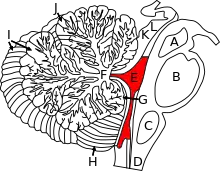

| T2-weighted sagittal MRI of Dandy–Walker variant (DWV) with dysplasia of the pons and cerebellar vermis in an 8-year old | |

Dandy–Walker malformation (DWM), also known as Dandy–Walker syndrome (DWS), is a rare congenital brain malformation in which the part joining the two hemispheres of the cerebellum (the cerebellar vermis) does not fully form, and the fourth ventricle and space behind the cerebellum (the posterior fossa) are enlarged with cerebrospinal fluid. Most of those affected develop hydrocephalus within the first year of life,[6] which can present as increasing head size, vomiting, excessive sleepiness, irritability, downward deviation of the eyes and seizures.[4] Other, less common symptoms are generally associated with comorbid genetic conditions and can include congenital heart defects, eye abnormalities, intellectual disability, congenital tumours, other brain defects such as agenesis of the corpus callosum, skeletal abnormalities, an occipital encephalocele or underdeveloped genitalia or kidneys.[5] It is sometimes discovered in adolescents or adults due to mental health problems.[5][6]

Pathophysiology

The cerebellum begins forming at the fifth week of embryonic development. It differentiates at the top of the metencephalon, while the pons (in the brainstem) differentiates at the bottom, separated by the fourth ventricle. The cerebellar hemispheres form from the rhombic lips on the forward surface of the fourth ventricle, which expand and roll over to fuse in the midline to form the cerebellar vermis by the 15th week. If this process does not complete, the cerebellar vermis will not form fully. This long period of development of the cerebellar vermis makes it particularly vulnerable to disruptions.[6]

In DWM, the fourth ventricle opens up into and is continuous with almost the entire posterior fossa subarachnoid space.[6]

Criteria and classification

The precise diagnostic criteria and classification systems of DWM are not agreed upon, and significant dispute exists as to which terms or criteria should be used.[5][6][12] The core criteria of DWM are hypoplasia of the cerebellar vermis and an enlarged fourth ventricle and posterior fossa (the space behind the cerebellum), though the specific degree of hypoplasia or cystic enlargement for diagnosis of DWM is not agreed upon.[7] Additionally, there are several similar conditions which have at various times been grouped with DWM on a continuum by some authors and separated as distinct by others, further complicating diagnosis.[6][8]